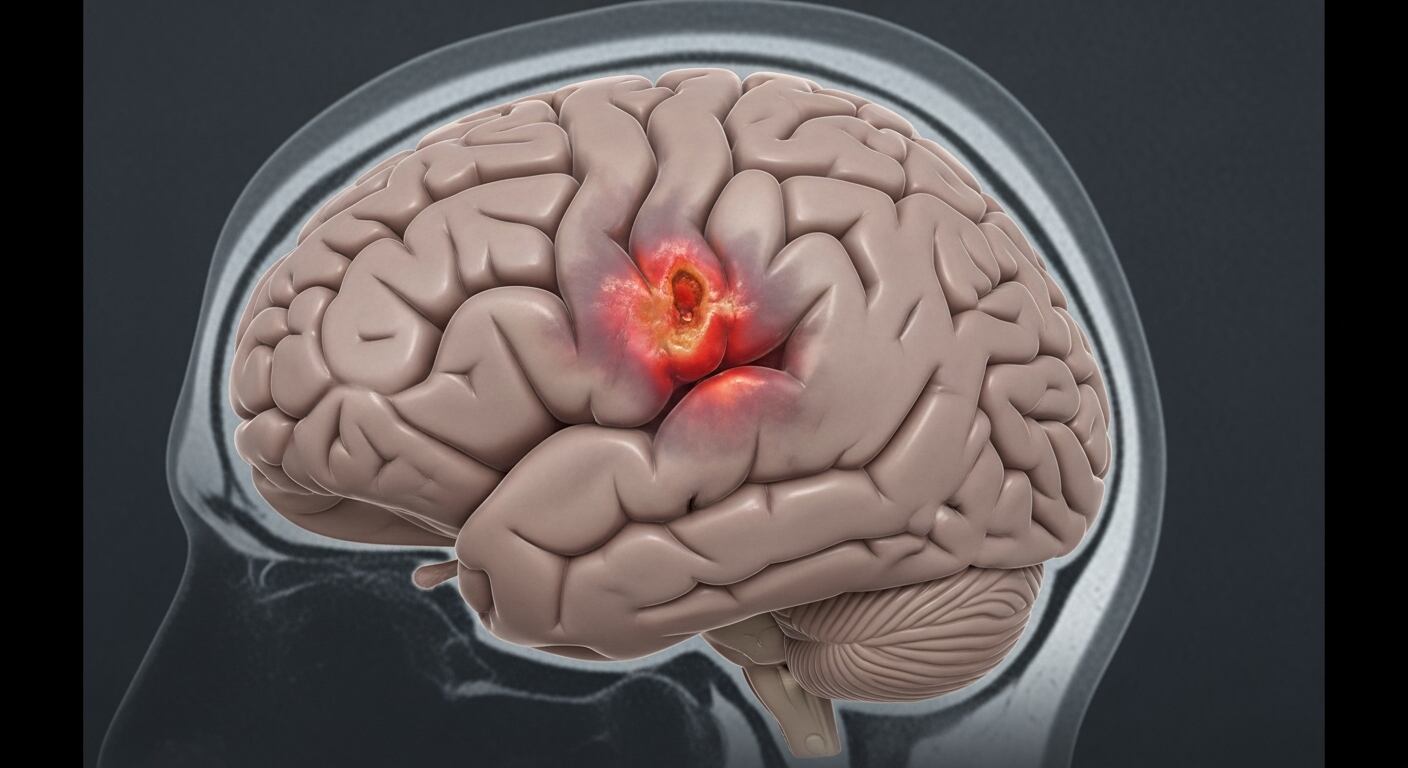

La barrera hematoencefálica (BHE) cumple una función central: permite el paso de nutrientes esenciales al cerebro y bloquea toxinas y células inflamatorias que podrían desencadenar reacciones dañinas.

Los científicos constataron que, cuando esta barrera se vuelve permeable, pierde su capacidad de protección y se asocia al deterioro cognitivo y neurológico de los exdeportistas, facilitando procesos degenerativos como la encefalopatía traumática crónica (ETC), la enfermedad de Alzheimer y otras formas de demencia.

El estudio incluyó también el análisis de tejido cerebral post mortem de atletas diagnosticados con ETC, confirmando la presencia de una “fuga” persistente que permitía la entrada de proteínas inflamatorias. Estas proteínas, entre ellas la p-Tau —tóxica y asociada al Alzheimer—, desencadenan una cascada de daños que agravan la degeneración cerebral.

Por primera vez se comprobó que la “puerta de seguridad” del cerebro sigue sufriendo “fugas” años después de abandonar el deporte de contacto. Esta alteración permite la infiltración de proteínas tóxicas que se vinculan al mal de Alzheimer y otras formas de demencia.